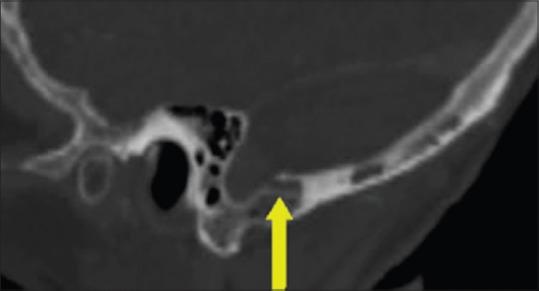

Several cadaveric studies demonstrate reliable localization of the transverse sinus and the transverse sigmoid junction (TSJ). These studies use the line drawn from the inion to the posterior root of the zygoma (IZ) and the asterion, respectively. We investigated how the size difference between the right and left transverse sinuses (TS) and sigmoid sinuses (SS) affected the accuracy of their respective superficial landmarks, particularly with regards to where this relationship may result in unsafe and/or complicated surgical access.

We utilized Vitrea software to render three-dimensional images based on computed tomographic angiography (CTA). We measured the relationship between the TS and SS to their respective superficial landmarks.

We analyzed 50 patients in this study. The distal TS was found caudal to the inion-to-zygoma (IZ) line on average by 5.0 ± 4.3 mm on the right and 6.4 ± 9.3 mm on the left. The mid TS was found cranial on average 3.5 ± 5.7 mm on the right and 3.2 ± 6.0 mm cranial on the left to the superior nuchal line (SNL). The distance from the asterion to the SS was 11.5 ± 2.4 mm medial on the right and 12.1 ± 4.4 mm medial on the left. The average distance was greater on the left than the right when using the IZ landmark. This was directly proportional to the size difference of the sinuses ( = 0.15, = 0.03).

Statistically significant differences between the right and left TS and SS were seen in terms of size. This appeared to correlate nicely to the differences observed between the locations of the TSs' and their respective superficial landmarks.

多项尸体研究表明,横窦和横乙状窦交界处(TSJ)的定位可靠。这些研究分别使用从枕外隆凸至颧骨后根(IZ)的连线和星点。我们研究了左右横窦(TS)和乙状窦(SS)之间的大小差异如何影响其各自表面标志的准确性,特别是这种关系可能导致不安全和/或复杂手术入路的情况。

我们利用Vitrea软件根据计算机断层血管造影(CTA)生成三维图像。我们测量了TS和SS与其各自表面标志之间的关系。

我们在本研究中分析了50例患者。发现右侧远端TS平均位于枕外隆凸至颧骨连线(IZ)下方5.0±4.3mm处,左侧为6.4±9.3mm。右侧TS中部平均位于上项线(SNL)上方3.5±5.7mm处,左侧为3.2±6.0mm。从星点到SS的距离右侧内侧为11.5±2.4mm,左侧内侧为12.1±4.4mm。使用IZ标志时,左侧的平均距离大于右侧。这与窦的大小差异成正比( = 0.15, = 0.03)。

左右TS和SS在大小方面存在统计学显著差异。这似乎与TS位置及其各自表面标志之间观察到的差异密切相关。